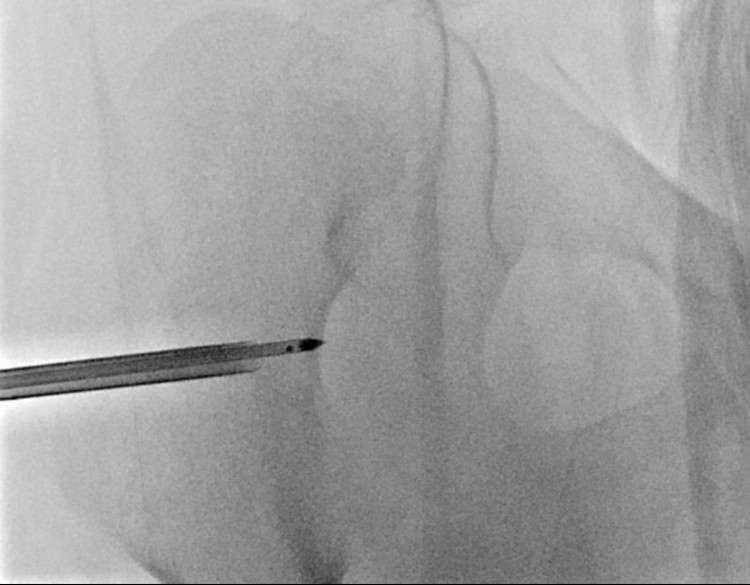

Sau khi thăm khám tại nhiều bệnh viện tuyến tỉnh và trung ương, các bác sĩ xác định nguyên nhân là do một u xương lành tính (osteoid osteoma). Kích thước khối u chỉ 5mm nhưng nằm sâu ở mặt sau và trong của cổ xương đùi , nằm trong bao khớp và sát với bề mặt của khớp háng – vị trí rất khó tiếp cận.

Khối u nằm ở một vị trí cực kỳ khó: mặt sau và trong của cổ xương đùi bên phải, hoàn toàn trong bao khớp. Phẫu thuật gần như không thể vì nếu mổ mở để lấy u, cháu bé có nguy cơ cao bị tổn thương mạch máu nuôi xương, dẫn tới hoại tử chỏm xương đùi, thậm chí phải thay khớp háng khi còn rất nhỏ tuổi.

TS.BS Nguyễn Ngọc Cương (Trưởng khoa Can thiệp điện quang, Bệnh viện Đại học Y Hà Nội), người trực tiếp thực hiện ca can thiệp chia sẻ: "Đây là một trong những vị trí khó nhất do nằm sâu, sát các mạch máu nuôi xương và trong bao khớp. Việc tiếp cận đòi hỏi độ chính xác tuyệt đối. Nếu đi lệch chỉ vài mm, có thể gây chảy máu khớp hoặc tổn thương sụn khớp”.

Can thiệp tiến hành bằng mê nội khí quản, khoan xương qua cổ xương đùi để vào đến khối u xương dưới định vị bằng Siêu âm, Fluoscopy và Conbeam CT. Đốt sóng cao tần bằng kim có đầu đốt dài 0,7 cm.